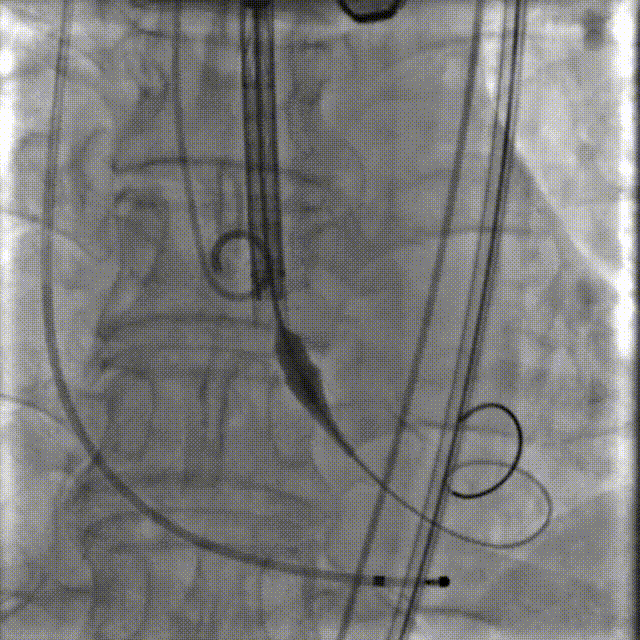

李有金教授 宁夏回族自治区人民医院 “随着人口老龄化加剧,主动脉瓣狭窄患者数量逐年增多,其中高龄、合并多种基础疾病的复杂病例占比不断提升。经导管主动脉瓣置换术(TAVR)作为微创治疗技术,已成为此类患者的重要治疗选择。对于高龄、有恶性肿瘤病史的患者而言,手术的安全性、微创性与长期疗效同等重要,既要最大程度降低手术创伤与并发症风险,也要确保瓣膜的耐用性与患者术后生活质量。 全球首款预装干瓣ProStyle A®的临床应用,为复杂病例治疗提供了全新解决方案。该瓣膜无需术中戊二醛冲洗,大幅缩短了手术操作时间,尤其适合高龄、心功能欠佳的患者。其独特的抗钙化工艺与优化的瓣架设计,既保证了瓣膜的长期耐久性,又能有效规避冠脉风险,为患者的“全生命周期管理”奠定了坚实基础。” 病例简介 现病史:患者半月余前突发抬头时一过性头晕,持续数秒钟,每日发作3-5 次,伴天旋地转感,症状可自行缓解。2025年12月12日就诊于外医院,心脏彩超提示“主动脉瓣狭窄(重度)并关闭不全(轻度),左室壁增厚,升主动脉增宽,左心室收缩功能正常,舒张功能减退”,建议转上级医院诊治。为求进一步治疗,患者就诊我院,门诊以“主动脉瓣狭窄”收住入院。 既往史:胃癌,胃大部切除术后五年。 临床诊断:“1.主动脉瓣狭窄伴有关闭不全(重度狭窄伴轻度关闭不全);2.主动脉瓣钙化;3.肥厚性非梗阻性心肌病;4.心功能不全;心功能III级(NYHA分级);5.升主动脉扩张;6.胃恶性肿瘤个人史” 术前CT评估显示:Type-1型二叶瓣,R-N钙化粘连,瓣叶重度钙化,主要分布在无冠窦瓣叶游离缘、R-N对合缘粘连处及右冠窦基底部;钙化积分933.2mm³;主动脉瓣环直径26mm,LVOT 27.6mm;双侧瓣叶开口高度可,左冠开口高度22.0mm,右冠开口高度20.0mm;主动脉水平夹角57.7°,左室内径偏小;主动脉弓部75.1°锐角弓;外周入路无明显迂曲及钙化,双侧股动脉内径可,右股中分叉。 手术策略 右侧股动脉为主入路,左侧为辅助入路,20F大鞘,股骨头中段穿刺;预装金仕生物 ProStyle A® AV26瓣膜,备29瓣膜,22mm球囊预扩;初始定位对齐瓣环上5mm超高位释放,释放过程中使瓣膜自然下滑至工作位,最终理想位置零位,利用瓣上锚定与封堵,规避冠脉风险;术前适当补液; 手术过程 Step1:主动脉根部造影; 主动脉根部造影 Step2:使用“先瑞达”22mm球囊预扩,无腰无漏,冠脉充盈良好; 球囊预扩 Step3:将ProStyle A®预装干瓣送至目标位置,初始定位后缓慢释放,观察瓣膜自然下滑至理想工作位; 定位 释放至工作位观察 Step5:瓣膜完全释放后,再次造影,显示瓣膜位置、形态良好,导管测平均跨瓣压差由术前60mmHg-降至1mmHg,冠脉血供正常; 最终造影 Step6:术后即刻超声监测,人工瓣膜位置固定,瓣叶启闭无受限,瓣周少量反流。 术后患者病情稳定,已于一周后出院。 结语 作为宁夏回族自治区心血管疾病诊疗的核心高地与区域医疗中心建设的标杆单位,宁夏回族自治区人民医院始终坚守“敬佑生命、救死扶伤”的医者初心,以“技术引领、学科兴院”为发展理念,在心脏大血管领域持续深耕,构建了集“精准评估-个性化方案-微创治疗-全程康复”于一体的诊疗体系。此次西北首例ProStyle A®预装干瓣植入手术的圆满成功,不仅是医院在复杂结构性心脏病介入治疗领域的又一突破性成果,更彰显了医院在引进前沿技术、转化创新器械、服务复杂重症患者方面的责任与担当。 Prostyle A®预装干瓣——助力临床最优化解决方案: 预装干瓣 便捷顺安:金仕生物专利抗钙化技术运用纳米技术去除组织内的细胞碎片和磷脂,封闭游离醛基,从根本上阻断了瓣膜钙化的多项因素,显著提升了瓣膜的耐久性;同时,相比较传统戊二醛保存方式,干式存储最大限度的保留心包的亲水亲油平衡,还原组织天然曲柔性,进一步保障了瓣叶开合,保证长期耐久性; 平衡径向支撑力:Prostyle A®瓣架网孔比例按照病例解剖结构的特殊设计,使瓣膜在狭窄最重的地方良好的撑开,同时避免对瓣环及周边组织的过度压迫,有效降低传导阻滞风险; 精准释放:底部桶状设计更易迅速锚定,协同释放张力小,助力最终精准释放; 过弓柔顺:较细的输送系统直径+亲水涂层,显著提升输送系统通过性,有效减少血管并发症的发生,内连鞘版本最小尺寸等效14F大鞘; 专家简介 李有金 宁夏回族自治区人民医院(点击查看专家详细简历) · END ·